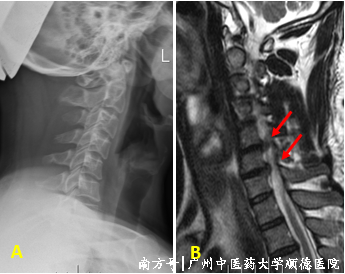

但在这四年里,黄先生的颈痛、左上肢麻痹疼痛经常反复发作,尤其在加班工作、劳累、看手机时间长了以后,症状就加重。近来,黄先生工作时突感左上肢动不了,又麻又痛,抬不起来,脖子歪着才会舒服点。经过再次检查结果显示短短四年,他的颈椎曲度反弓了!医生建议复查个磁共振。

↑ A 颈椎曲度反弓,B C5/6、C6/7椎间盘突出,神经受压。

↑ MRI提示C5/6、C6/7椎间盘突出,左侧神经受压,C6/7突出伴钙化。